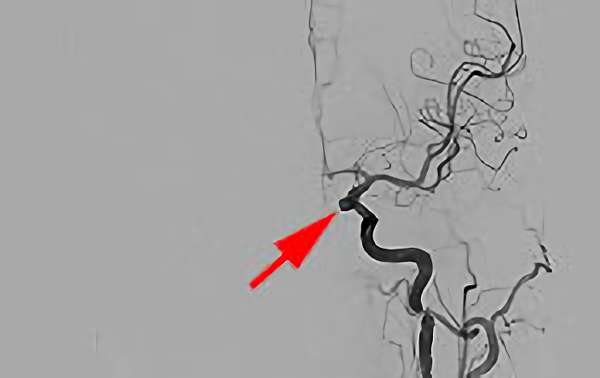

'26年4月

左後下小脳動脈瘤

80代

大阪府の病院

No.1631 手術後